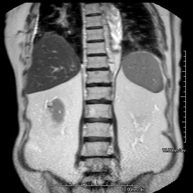

- RM d'Abdomen

Prova diagnòstica no invasiva que consisteix en l'obtenció d'imatges d'alta definició anatòmica de l'abdomen mitjançant l'ús d'un camp electromagnètic i ones de ràdio (amb un emissor i un receptor). No utilitza radiació ionitzant. En aquesta exploració s'inclouen el fetge, el pàncrees, la melsa, la via biliar, la vesícula biliar, les glàndules suprarenals, els ronyons, l'aorta abdominal, la vena cava inferior, l'estómac, el duodè, etc. En alguns casos caldrà emprar contrast paramagnètic (Gadolini) per caracteritzar les lesions. - RM Pelvis femenina

Prova diagnòstica no invasiva que consisteix en l'obtenció d'imatges d'alta definició anatòmica del fetge mitjançant l'ús d'un camp electromagnètic i ones de ràdio (amb un emissor i un receptor). No utilitza radiació ionitzant. Es realitza per estudiar qualsevol lesió localitzada en el fetge. Normalment es requereix l'ús de contrast paramagnètic (Gadolini) per caracteritzar les lesions. És necessari realitzat la prova en dejú (6 hores). - RM de Ronyons

Prova diagnòstica no invasiva que consisteix en l'obtenció d'imatges d'alta definició anatòmica d'ambdós ronyons mitjançant l'ús d'un camp electromagnètic i ones de ràdio (amb un emissor i un receptor). No utilitza radiació ionitzant. Es realitza per estudiar qualsevol lesió localitzada en ambdós ronyons. Normalment es requereix l'ús de contrast paramagnètic (Gadolini) per caracteritzar les lesions. - RM Glándulas Suprarrenales